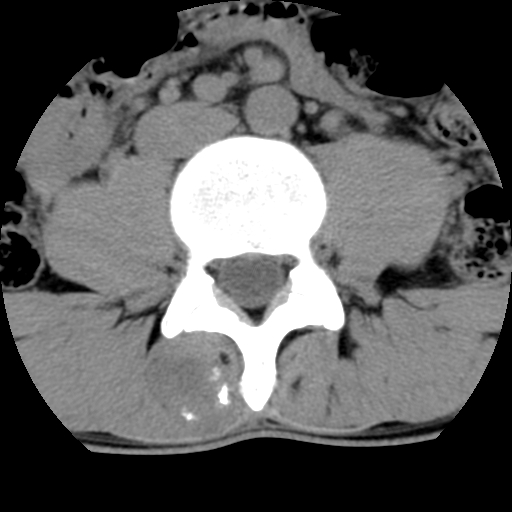

标题: CT16890:男,腰背痛.

男,腰背痛

本人诊断1tb2包虫,请会诊

1)右侧竖脊肌稍低密度肿块伴钙化(性质待定),不排除肿瘤可能;建议行进一步检查。2)腰椎间盘突出。

1.右侧竖脊肌软组织肿块伴团块状钙化,首先考虑血管瘤可能性大;建议行进一步检查;2。腰椎间盘突出。